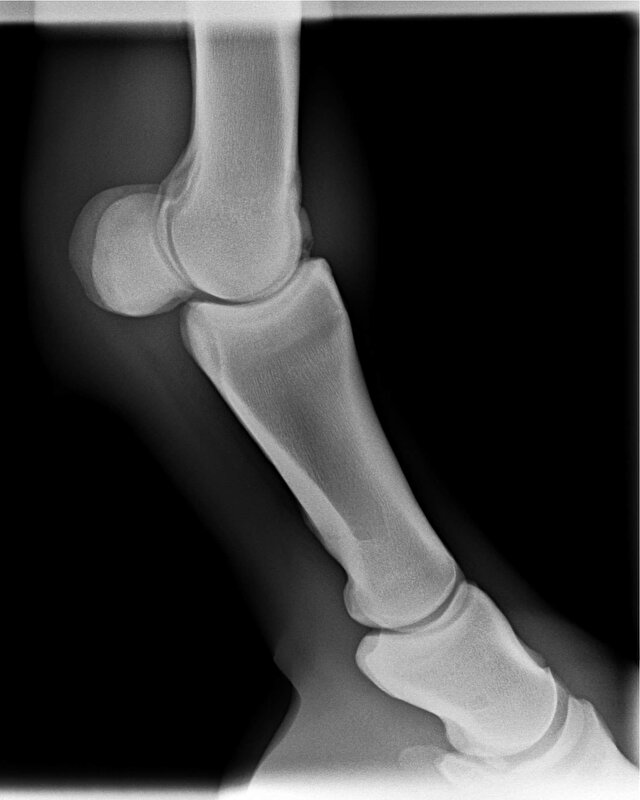

Het regeneratief vermogen is dus beperkt. De enige nu gebruikte behandeling voor regeneratie van kraakbeen is PRP (plaatjes rijk plasma). Een injectie van geprepareerd eigen bloed van het paard in het gewricht. (In het fysiologische proces van wondgenezing dienen bloedplaatjes, welke in het bloedstolsel aanwezig zijn, als primaire bron van biologisch actieve factoren. Bij het gebruik van PRP’s worden suprafysiologische concentraties bereikt van de hierboven genoemde groeifactoren die het reparatieproces door directe en indirecte mechanismen bevorderen)

Ik heb de indruk dat het botfragment bij het paard van TS dus vrij groot was. Gezien men ook het bot heeft moeten vlakken. Dan is de schade in het gewricht ook groter. Mogelijk zo groot dat geen herstel meer mogelijk is. Hoe lang je het paard ook rust geeft. Ik kan me niet precies visualiseren hoe het bij haar paard precies zit, maar dit is wat ik ervan weet.

Nu gaat het onderzoek naar kraakbeenherstel wel erg snel en mogelijk is er binnen een aantal jaren wel een betere behandeling. Ik weet wel dat onderzoek naar stamceltherapie bij kraakbeen (kraakbeenmatjes) nu in een soort pilotfase is beland.